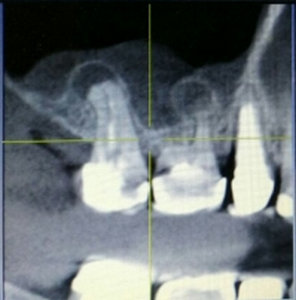

У меня обнаружили 2 кисты на 36 зубе. На одном корне киста маленькая, на втором большая. Снимок прилагается. Врач-терапевт сначала сказал, что нужно удалить кисту, а потом сказал лечить. Просверлил зуб, оставил открытым, сказал полоскать солевым раствором и принимать Кетарол.